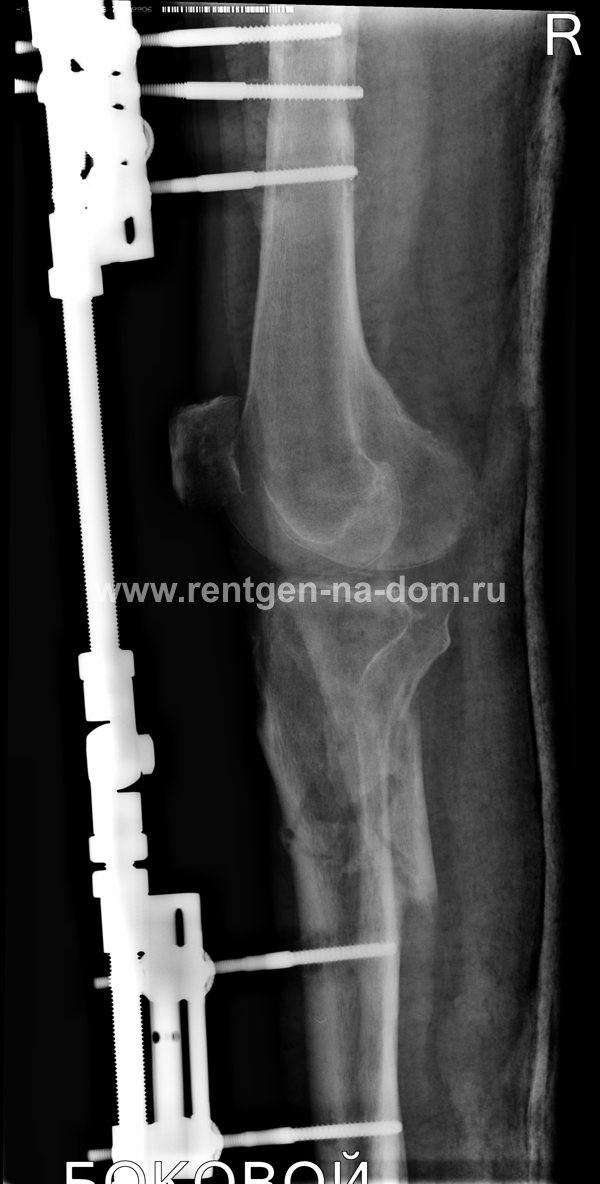

Решающее значение в установлении диагноза перелома шейки бедра имеет рентгенография тазобедренного сустава. У пожилых пациентов приведенные выше симптомы могут проявляться нечетко, а такие заболевания как инсульт или невропатия, вообще, не позволят поставить правильный диагноз без рентгена. Где сделать рентген? Перелом шейки бедра всегда сопровождается сильной болью, поэтому любые лишние движения оборачиваются новыми мучениями, а сопутствующие заболевания внутренних органов усугубляют ситуацию! Решение есть - воспользоваться уникальной услугой – цифровой рентген на дому. К вам приедет врач рентгенолог-травматолог, который выполнит весь комплекс лечебно-диагностических мероприятий и подробно расскажет, что делать дальше.

- иммобилизация при переломе шейки бедренной кости

- лечение перелома бедренной кости

Получение качественных рентгеновских снимков на дому предъявляет серьёзные требования к рентгеновской аппаратуре. Далеко не каждый переносной рентгенаппарат позволяет получать снимки необходимого качества, чтобы достоверно поставить диагноз. Используемый нами рентгенаппарат АРА 110/160 в комплексе с компьютерным радиографом позволяет получать цифровые рентгеновские снимки высокого качества у пациентов различной комплекции и является уникальной услугой в Санкт-Петербурге, предоставляемой на дому.